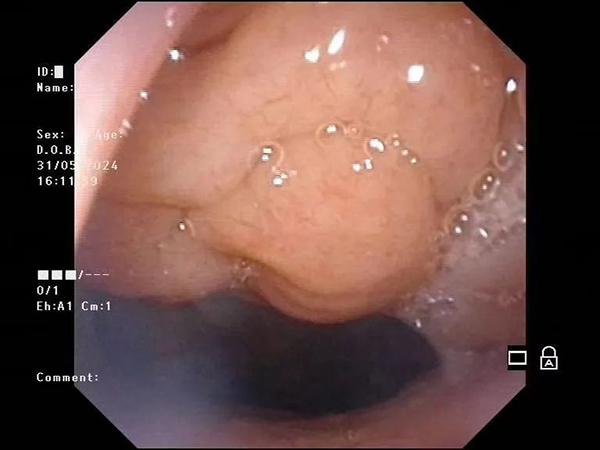

镜下影像示例:

镜下小儿鼻窦炎